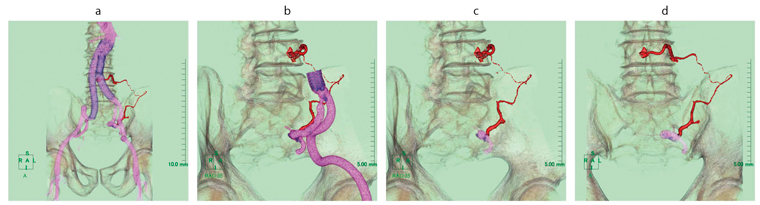

図4 aが完成した超選択的CTAである。図2と比較すると,主たる血管が抽出されず,非常にさびしい感じになっているが,これが術者として欲しい情報であった。角度やカット領域を変更して観察を行うと(図4 b〜d),責任動脈は,左腸腰動脈からの側副血行路より左第4陽動脈へ到達していた。途中に強い屈曲や細い箇所があるが,親カテーテルが左腸腰動脈に深く挿入できれば,マイクロカテーテルの通過は可能だと推測した。左内腸骨動脈は,左総大腿動脈からの同側アプローチでは角度などが簡単ではなさそうだったが,透視角度およびカテーテル形状などにて克服可能と推測した。以上のことからTAEの適応と判断し,治療に踏み切った。

図4 超選択的CTA

a:全体像の正面 b:左総腸骨動脈までカットを入れた右前斜位

c:左内腸骨動脈までカットを入れた右前斜位 d:左内腸骨動脈までカットを入れた正面